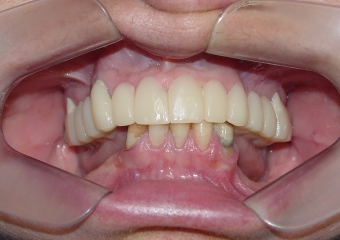

Próteses Fixas Provisórias em Setembro de 2015 - Clínica Cliniface

Próteses Fixas Provisórias em Setembro de 2015